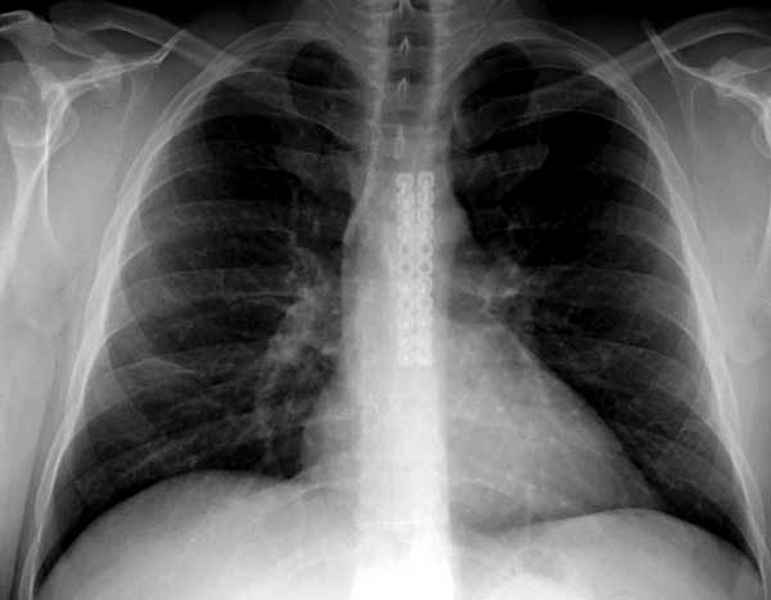

Юра, интересно, насколько такой остеосинтез контролирует степень репозиции, а то у меня имеются снимки девочки 11 лет, направленной ко мне на консультацию из одной из республик бывшего союза.

После торакальной операции, по-видимому, сильно натянули проволоку, и в результате получился захлест отломков в друг друга.

Оперировавший хирург предлагает подождать, а родителей беспокоит проблема прогрессирующей ассиметрии лица, как при кривошее.

С такими продольными несращениями мне не приходилось иметь дело, поэтому направил в один из центральных институтов детской ортопедии России.

А простые посттравматические ложные суставы грудины приходилось оперировать с ограничителем сверла и с фиксацией 2.4 мм пластинами с угловой стабильностью.